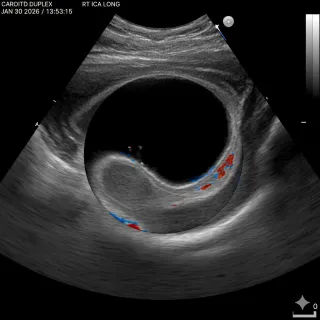

Doppler ultrasound images can look confusing at first—especially when you see bold reds and blues or a jagged “heartbeat” graph on the screen. This blog breaks it all down in plain language: what the ... ...more